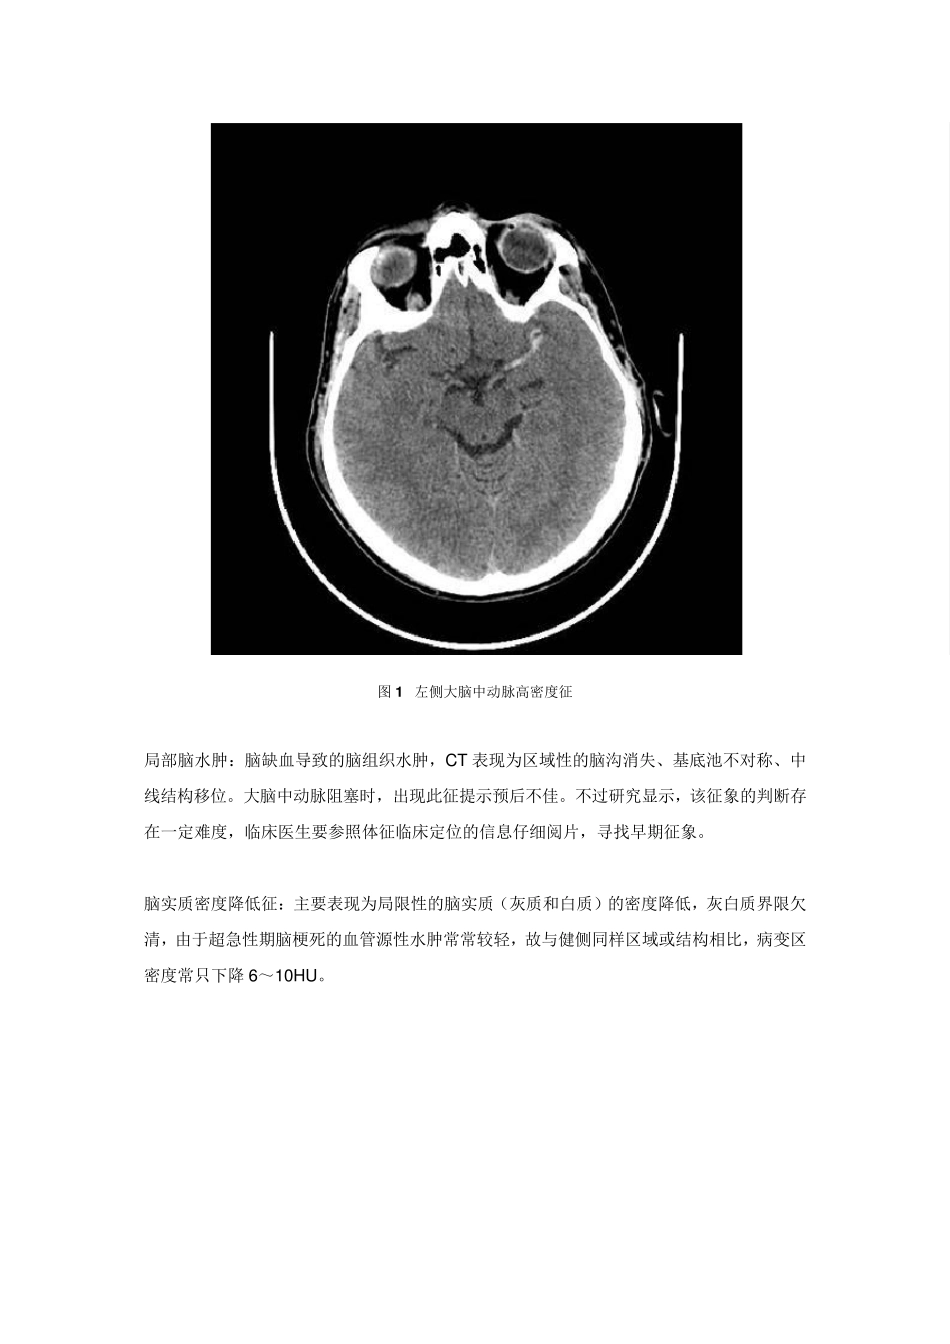

看 图 说 话 : 缺 血 性 脑 卒 中超急性 期的影像学特点 导读:对于疑为缺血性脑卒中的患者而言,CT是临床上首选的辅助检查,CT灌注、MRI等技术的应用更是为缺血性脑卒中的早期诊治提供了莫大帮助。本文将结合影像学资料,对缺血性脑卒中超急性期的影像学特点进行梳理。 典型的缺血性脑卒中表现可分为超急性期、急性期、亚急性期和慢性期。临床上,人们通常将发病 6 小时之内的缺血性脑卒中病例归为超急性期,一些影像学文献则将 12 小时之内的病例也包括在内。在超急性期对患者进行快速识别,排除非缺血性脑卒中神经系统疾病,并明确梗死区域,有助于尽早确定下一步的治疗方案。 CT 作为一种急症,缺血性脑卒中的诊治需要争分夺秒。头部 CT 平扫方便快捷,是急性脑卒中患者的首选,然而在缺血性脑卒中的早期,CT 的灵敏度有限。急诊 CT 的主要目标是: ➤ 排除颅内出血,以确定患者是否可以溶栓治疗; ➤ 寻找任何早期脑梗死的特征改变; ➤ 排除类似脑卒中的其他颅内病变,例如肿瘤。 超急性期时,CT 上脑实质并不会出现非常明显的密度改变,但超急性期的几个征象对于早期诊断意义重大。 动脉致密征:多发生于大脑中动脉、颈内动脉、椎动脉,表现为一段动脉密度增高。大脑中动脉显示此征象较多,可称之为“大脑中动脉高密度征”。CT 上常显示大脑中动脉水平段位于侧裂之内,在脑脊液的衬托下呈条状软组织密度影,CT 值为42~53Hu,而梗死后 CT值可达 70~90Hu。该征象并不特异,也可见于无脑梗死的糖尿病和高血压患者,动脉壁发生钙化时密度也可增高。 图1 左侧大脑中动脉高密度征 局部脑水肿:脑缺血导致的脑组织水肿,CT 表现为区域性的脑沟消失、基底池不对称、中线结构移位。大脑中动脉阻塞时,出现此征提示预后不佳。不过研究显示,该征象的判断存在一定难度,临床医生要参照体征临床定位的信息仔细阅片,寻找早期征象。 脑实质密度降低征:主要表现为局限性的脑实质(灰质和白质)的密度降低,灰白质界限欠清,由于超急性期脑梗死的血管源性水肿常常较轻,故与健侧同样区域或结构相比,病变区密度常只下降 6~10HU。 图2 老年患者,突发左侧偏瘫,即时CT平扫(左图)显示右侧额叶大脑中动脉供血区局部脑沟消失、脑回稍肿胀,灰白质边界模糊,密度稍减低,侧脑室前角轻度受压;3 日后复查 CT(右图),显示病灶区域密度明显减低,右侧侧脑室受压明显,中线向左移位 CT灌 注 和血管造影...